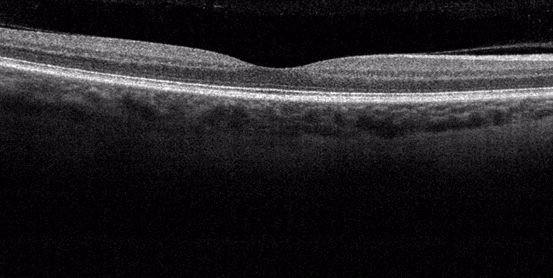

Optická koherenční tomografie - OCT

Jedná se o neinvazivní vyšetření, které nezatěžuje pacienta. Pracuje na podobném principu jako ultrazvuk. Místo zvukové vlny je použit světelný paprsek. Umožňuje opakovaně vyšetřit sítnici na úrovni histologického řezu. Na snímcích jsou patrny jednotlivé vrstvy sítnice. OCT je důležitá ke zjištění diabetického makulárního edému a celé řady dalších onemocnění žluté skvrny (makuly).

Obr. OCT obraz normální sítnice